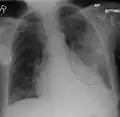

| A chest X-ray showing a very prominent wedge-shape bacterial pneumonia in the right lung | |

AP CXR showing left lower lobe pneumonia associated with a small left sided pleural effusion -

AP CXR showing right lower lobe pneumonia -

AP CXR showing pneumonia of the lingula of the left lung -

Right upper lobe pneumonia as marked by the circle. - Left upper lobe pneumonia with a small pleural effusion.

- Right lower lobe pneumonia as seen on a lateral CXR